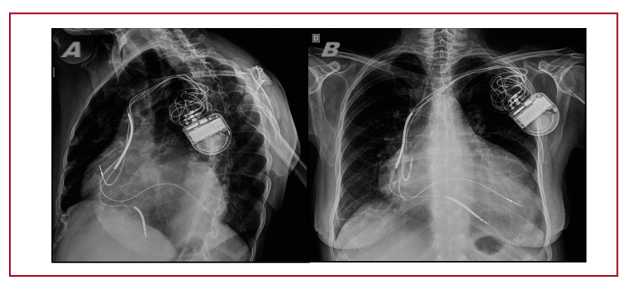

Introducción: La terapia de resincronización cardíaca presenta una tasa de un 25%-30% de pacientes “no respondedores”. La resincronización endocárdica, en la que el catéter del ventrículo izquierdo se implanta en el endocardio, sería una alternativa para estos pacientes, aunque su evolución a largo plazo no ha sido investigada.

Métodos: Se incluyeron pacientes implantados según los criterios para resincronización, usando la técnica Jurdham, con más de 6 meses desde el implante. Todos eran respondedores clínicos.